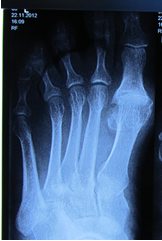

При подтверждении наличия патологии методами лучевой визуализации и отсутствии показаний к госпитализации пациенту нужно знать, как лечить артроз стопы в домашних условиях. Терапия занимает от 1 до 9 месяцев. Длительный срок объясняется непрерывным участием этого сегмента опорно-двигательного аппарата в активности человека на протяжении дня. Важно безошибочно определить, на какой стадии артроз стопы – лечение в домашних условиях приемлемо только при хроническом течении болезни или на раннем этапе ее развития.